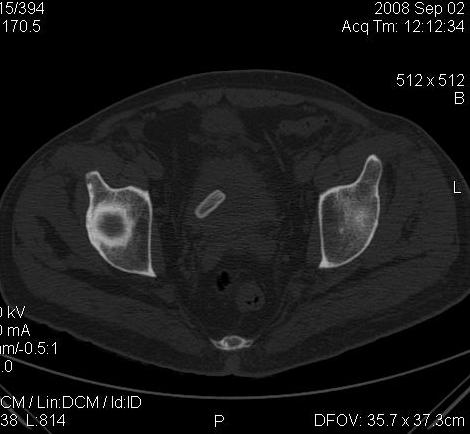

КТ Малого таза.

Что в мочевом пузыре? :?: ;)

Bladder foreign body0002.jpg

Я тоже так думал! Урологи выполнили цистоскопию, оказалось камень, такой причудливой формы.